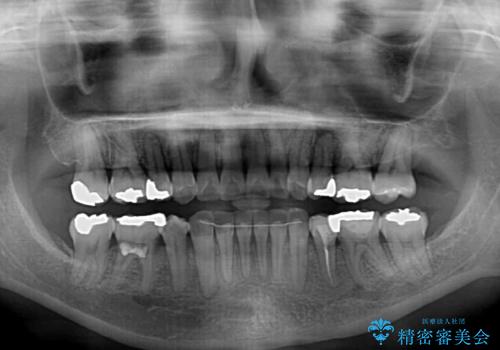

- 上下前歯の叢生を気にして来院された患者様です。

費用を抑え、期間もあまりかけずに治療をしたいとのことで、インビザライン・ライトを用いて矯正治療を行うこととしました。

矯正治療後には、下顎臼歯の目立つ銀歯をセラミックインレーにて修復治療を行いました。

インビザライン・ライトは、製作できるアライナーの枚数に制限があるため、移動可能な量に限りがあります。

軽微な後戻りの治療であったため、十分に治療を行うことができました。

口を開けたときに金属が見えなくなり、患者様には大変満足していただきました。